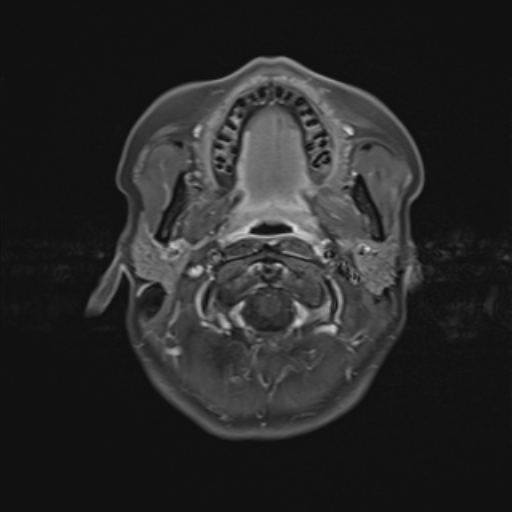

Descrizione Serie: t1_se_tra

Modalità: MR